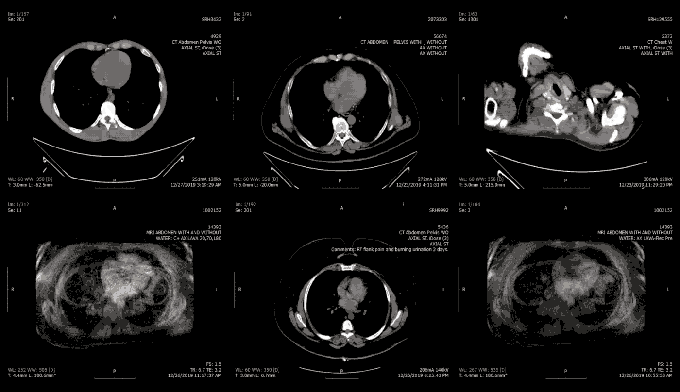

A billion medical images are exposed online, as doctors ignore warnings

This story was reported in partnership with health news site The Mighty. Every day, millions of new medical images containing the personal health information of patients are spilling out onto the internet. Hundreds of hospitals, medical offices and imaging centers are running insecure storage systems, allowing anyone with an internet connection and free-to-download software to … Continue reading A billion medical images are exposed online, as doctors ignore warnings